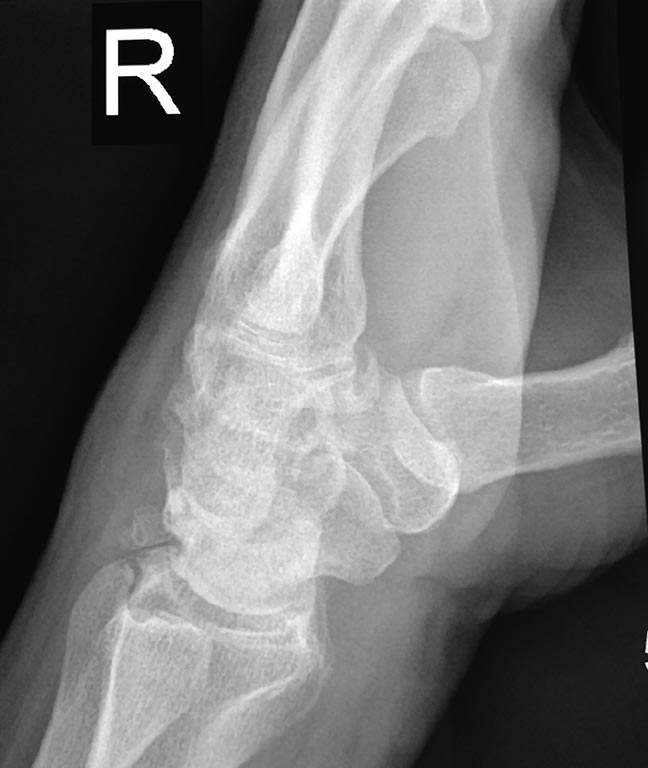

Для начала нужно говорить о тактике обследования. Если не КТ, то хотя бы косую проекцию для вывода ладьевидной кости. И боковую, конечно. Подобные долгоиграющие травмы чаще всего бывают при ложных суставах ладьевидной кости. А здесь уже есть артроз между лучевой и ладьевидной костями. Расширено расстояние между ладьей и полулунной. Скорее всего замешана ладьевидная кость.

Четкая картина SLAC, положительный симптом "кольца", Терри Томаса.

Согласен. Диастема Томпсона, а вот что с ней делать?

Боль преимущественно где в суставе? Похоже перелом боксера был и трехгранной кости. Плюс артроз есть.

"Боксерского" перелома не видно. Какой-то "кусок" кости "болтается", но непонятно, откололся от лучевой или от трехгранной. То есть налицо признаки бывшей травмы, но никак не аутоиммунного процесса.